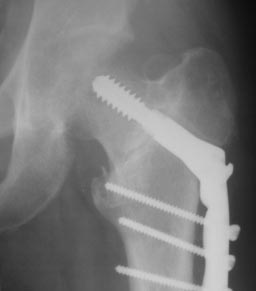

Уважаемые коллеги! Нужен совет. Появился такой больной Х., 23 года.

Травма 26.11.2013г. оступился в снегу, получил закрытый межвертельный

перелом левого бедра. Оперирован  09.12.2013г. Последние две недели

ходил с тростью, занимался ЛФК. Движения в левом тазобедренном суставе

безболезненные, незначительно ограничены.  Три  дня назад появились

ноющие боли в нижней трети левого бедра , субфебрилитет после физнагрузки.

Из обследования, пока, сделанные сейчас снимки.

Д-з: миграция конструкции, АНГБК?

Наши рекомендации:

1. Ходьба на костылях, не наступая на левую ногу.

2. Для уточнения консолидации перелома и степени аваскулярных нарушений КТ.

3. По результатам–  удаление фиксатора, костная пластика по каналу от

винта либо

остеотомия?